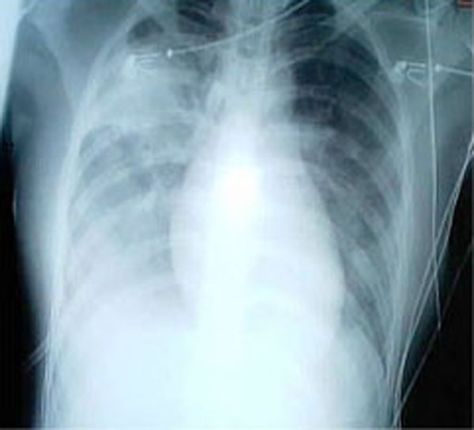

- CXR: Bilateral infiltrates, features of atypical pneumonia